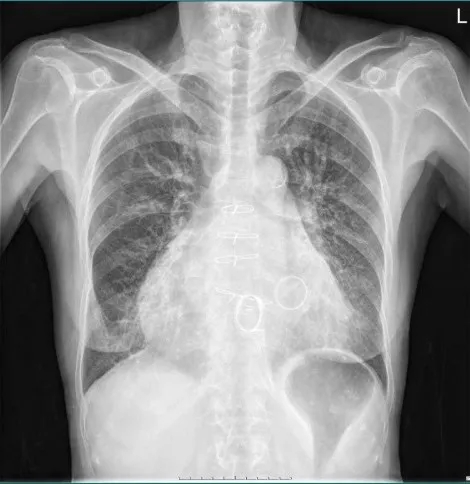

术前胸部CT评估

心脏瓣膜病术后:双肺纹理增多、增粗,双下肺野见少许斑片状模糊影;双肺门不大,主动脉结不宽,肺动脉段平直,心影增大,心胸比率:0.68。双侧膈面光整,双侧肋膈角锐利。心影内见术后环形金属密度影。 胸骨见术后内固定钢丝影,未见断裂、松动征象。